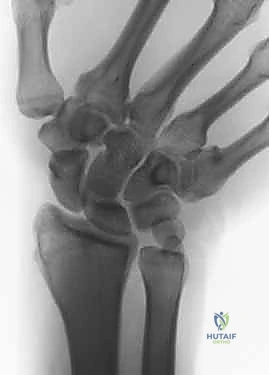

2. التصوير الشعاعي (X-Rays)

تُعد الأشعة السينية ضرورية لقياس "التباين الزندي". يتم أخذ صور بأوضاع محددة (مثل وضعية القبضة المشدودة) لإظهار أقصى درجات الضغط بين الزند والرسغ.

3. التصوير بالرنين المغناطيسي (MRI)

يُستخدم الرنين المغناطيسي عالي الدقة لتقييم الأنسجة الرخوة. يساعد هذا الفحص الدكتور هطيف في رؤية مدى تضرر المجمع الغضروفي الليفي الثلاثي (TFCC) ووجود أي استسقاء أو تكيسات داخل عظام الرسغ نتيجة الضغط المزمن.